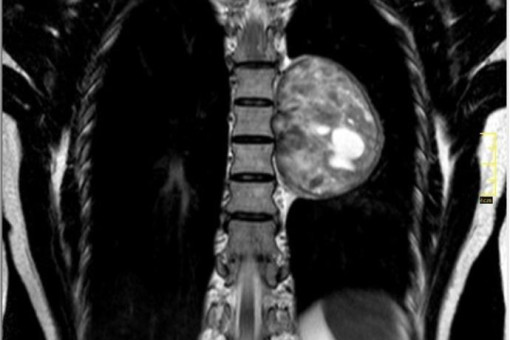

О гигантской опухоли жительница Новосибирска Вероника узнала случайно во время планового обследования. Опасность представлял не только размер образования, но и его расположение.